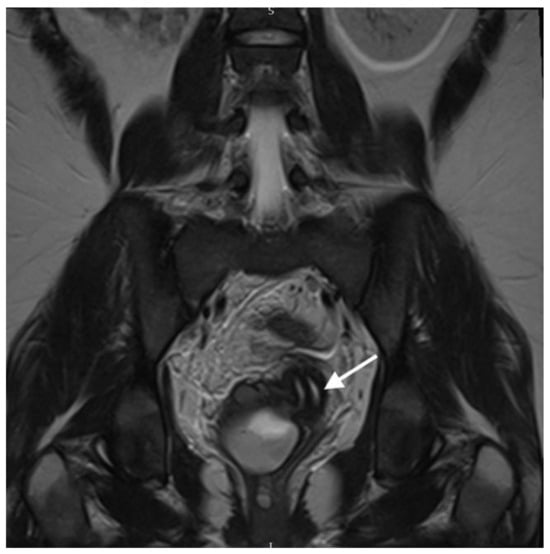

Axial T2-weighted MR image demonstrates uterus didelphys (two uterine cavities indicated by white arrows). A 21-year-old woman presented with lower abdominal and back pain, mainly located on the right side. The pain was constant and progressively worsened over a six-day period. She also reported episodes of vomiting over the last two days, constipation and a loss of appetite. Additionally, she had a previous assessment in A + E five days prior to this admission, where she was diagnosed with a chest infection and was treated with Co-amoxiclav. Her previous medical history and family history were unremarkable, she had never had any previous surgeries, had never conceived and was not allergic to any medication. Initially, she was assessed by members of the A + E team and was referred to the surgical team to exclude appendicitis or mesenteric adenitis. Upon examination, her abdomen was soft with voluntary guarding on the right iliac fossa. She was pyrexial (T: 38.1 °C), tachycardic (HR: 129 bpm), tachypnoeic (RR: 19), with normal blood pressure (BP: 119/80 mmHg) and oxygen saturation levels (SO2: 98%). Biochemical and haematological investigations revealed elevated CRP (>320 mg/L), white cell count (WCC: 16 × 109/L) and platelets levels (405 × 109/L). The liver and kidney functions were normal. Venous blood gas indicated a pH of 7.35 and lactate levels of 1.3 mmol/L. The urine sample indicated the presence of leucocytes, protein and blood. The urine pregnancy test was negative. The patient underwent a CT of her abdomen/pelvis after the initial surgical review. It revealed a large complex pelvic collection, measuring 7 × 6 × 10 cm, arising from the right adnexa, with the inflammatory process extending into the uterus. The CT also suggested incidental right renal agenesis, which the patient was not aware of. The findings were suggestive of a tubo-ovarian abscess (TOA), and the patient was started on intravenous ceftriaxone and metronidazole, as per the unit’s protocol. Due to the CT scan findings, the patient was then referred to the gynaecology team. Her gynaecological history indicated a menarche at 10 years of age. Her periods were regular, but she reported significant dysmenorrhea and heavy menstrual bleeding. Clinical examination including a speculum exam revealed that the cervix was difficult to visualise, since it was deviated to the left. A purulent foul-smelling discharge was also noted as well as a fullness on the anterior fornix, but no signs of significant tenderness were present at the time of the examination. After the gynaecological assessment, a pelvic ultrasound was requested to further characterize the pelvic mass. TVUSS was performed approximately 24 h after the CT, while the patient remained febrile. The sonographic assessment revealed the collection, previously attributed to the TOA, but the additional finding of uterus didelphys with two cervices was also noted. The combination of renal agenesis and uterine abnormality raised the possibility of a Müllerian abnormality; thus, an abdomen/pelvis MRI with contrast was requested in order to confirm the diagnosis. The MRI report confirmed that there was a double uterus and cervix and further added that there was a longitudinal vaginal septum (U3bC2V2 based on the ESHRE/ESGE classification [1]).

Coronal T2-weighted MR image shows 2 cervical canals (White arrow indicates the two cervical canals. The right-sided cervix leads to the obstructed haematopyocolpos). OHVIRA syndrome, also known as Herlyn–Werner–Wunderlich syndrome, is a rare uterine and renal congenital abnormality which is characterized by an obstructed hemivagina and ipsilateral renal agenesis [2]. The exact prevalence of the syndrome has not been yet estimated, but it has been reported that it accounts for 0.16–10% of Mullerian abnormalities, the incidence of which is 2–3% of the population [3]. Assessment via pelvic ultrasound in combination with MRI helps to establish an accurate clinical diagnosis [4]. In the majority of cases, pubertal women are more likely to be identified with the syndrome, since the onset of menstrual periods might lead to hematometra and/or delayed menarche. However, in cases of partial obstruction, the diagnosis can be elusive, often taking years to be established, leading, at times, to women presenting in adulthood with symptoms resembling pelvic infection and endometriosis [2]. Septectomy remains the treatment of choice and should be performed in all affected patients. Knowledge of this rare condition and maintaining high levels of suspicion is critical in these cases [5,6].